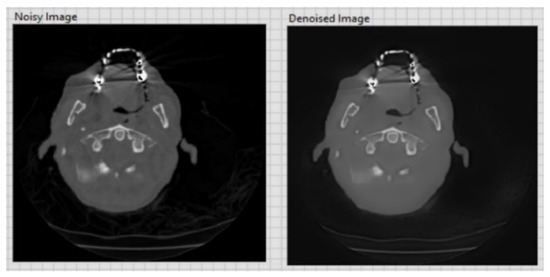

| CT image (Figure 6) 256 × 256 | 26.01 | 0.05 |

| CT image (Figure 7) 256 × 256 | 20.15 | 0.1 |

| CT image (Figure 8) 256 × 256 | 20.13 | 0.1 |

| CT image (Figure 9) 256 × 256 | 26.09 | 0.05 |

| CT image (Figure 10) 256 × 256 | 20.18 | 0.1 |

| CT image (Figure 11) 256 × 256 | 26.15 | 0.05 |